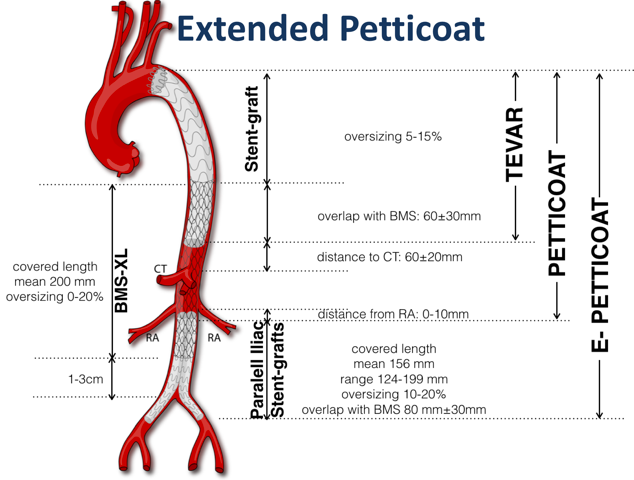

2022-11-07Lekarze Kliniki Chirurgii Naczyniowej, Ogólnej i Angiologii naszego szpitala dokonali pierwszego w kraju, całkowicie przezskórnego wszczepienia modyfikowanego stent-graftu. Była to operacja ratująca życie, a pomocna przy tym - technika druku 3D.

Dostępy całkowicie przezskórne (bez cięcia skóry) wykonuje tylko kilka ośrodków w Polsce i jest to metoda coraz częściej preferowana, ale głównie do mniej skomplikowanych przypadków. Tym razem do szpitala na Pomorzanach trafił 75-letni pacjent z objawowym tętniakiem okołotrzewnym (aorty piersiowo-brzusznej) - bolesnym, grożącym pęknięciem, a zatem stanowiącym zagrożenie życia. Dodatkowo chory nie miał szans na skorzystanie ze standardowego stent-graftu branchowego (z doszywanymi „rękawkami” na naczynia) czy fenestrowanego (z wyciętymi „okienkami” na naczynia) zamawianego u producenta z powodu występujących u niego dodatkowych naczyń, odchodzących od aorty (osobne ujście tętnicy wątrobowej). Nie mógł też czekać na wyprodukowanie stent-graftu szytego dla niego na miarę, bo trwałoby to 8-12 tygodni, a bolesność tętnika świadczyła, że rychło pęknie. Groziło to śmiercią pacjenta.

Leczenie stent-graftami modyfikowanymi jest w domeną naszych lekarzy Kliniki Chirurgii Naczyniowej, Ogólnej i Angiologii, którzy wypracowali wysokiej jakości standard postępowania w użyciu tej metody. Wykorzystując model aorty danego pacjenta, wydrukowany techniką 3D, modyfikują własnoręcznie, już na sali operacyjnej standardowe stent-grafty i dopasowują je indywidualnie do anatomii operowanego pacjenta. Po co? Bo mimo ogólnej takiej samej budowy każdego z nas, układ naczyń krwionośnych, ich budowa, odległości między poszczególnymi naczyniami różnią się u każdego człowieka. Dlatego dla efektywności działania wszczepianego, standardowego stent-graftu – proteza ta powinna być dopasowana do budowy chorego. Chirurdzy naczyniowi USK-2 są jedynym zespołem w Polsce, który tego typu zabiegi wykonuje rutynowo, również w przypadkach nagłych. Jednak taki sposób leczenia, jak i wszelkie inne zaawansowane procedury aortalne, wymaga licznych, często trudnych dostępów naczyniowych (np. nacięć w pachwinach, rękach i klatce piersiowej) – tj. cięć i operowania „na otwarto”. Dla chirurga taka operacja jest łatwiejsza, bo pole operacyjne jest widoczne jak na dłoni. Ale dla pacjenta dochodzenia do formy po takiej operacji jest długotrwałe, bolesne i mało komfortowe. Dlatego użycie przez szczecińskich lekarzy wyłącznie dostępu przezskórnego (bez cięcia) w leczeniu tętnika jest dużym krokiem na przód w chirurgii naczyniowej, a fakt, że to pierwszy tego typu zabieg w Polsce to ogromny sukces naszych „naczyniowców” i świadczy o ich doskonałej technice operowania.

„Modyfikacja stent-grafu naszą, ‘szczecińską metodą’ pozwoliła na pokonanie technicznych trudności, dostosowanie protezy do chorego i wykonanie zabiegu „od ręki”. Zastosowaliśmy modyfikację stent-graftu z okienkami na cztery naczynia trzewne - mówi dr hab. n. med. Arkadiusz Kazimierczak, który wraz z dr. n. med. Pawłem Rynio operował mężczyznę. „Wykonanie przezskórne - dwa dostępy do tętnicy podobojczykowej na klatce piersiowej i obu udowych w pachwinach, zamiast jak dotychczas czterech - pozwoliło na zminimalizowanie urazu operacyjnego tak, że chory był w pełni uruchomiony już w pierwszej dobie po zabiegu i zapytał o termin wypisu ze szpitala – dodaje dr Paweł Rynio. Operacja odbyła się 20 września.

Obaj lekarze są członkami szczecińskiego Aortic Teamu, zespołu chirurgów naczyniowych i kardiochirurgów stosujących nowatorskie metody leczenia w przypadku tętniaków. Zespół planuje rozszerzenie wskazań do zabiegów całkowicie przezskórnych w leczeniu patologii łuku aorty. Pierwsze próby z ograniczeniem urazu operacyjnego w tym zakresie zostały już podjęte w przypadku innej operowanej chorej. Tym razem zastosowano dwa małe cięcia przy wymianie całego łuku aorty, zamiast jak dotychczas pięciu. Pacjentka również jest w dobrym stanie.

Tłumacząc obrazowo - tętniakiem aorty nazywany nadmierne (o ponad 50%) poszerzenie aorty, która jest największą tętnicą w ciele człowieka. Może ono występować na każdym jej odcinku, ale najczęściej występuje w części brzusznej. Przyczyną ich powstania jest odkładanie się blaszek miażdżycowych, nadciśnienie tętnicze, nadmierny, gwałtowny wysiłek czy uraz, czasem także wrodzone nieprawidłowości w budowie naczynia. Ryzyko wystąpienie tętniaka aorty brzusznej wzrasta z wiekiem i jest szczególnie wysokie u mężczyzn około 65. roku życia. Szczególnie niebezpieczne są tętniaki bezobjawowe, które w każdej chwili mogą grozić pęknięciem i prowadzić do zgonu chorego.